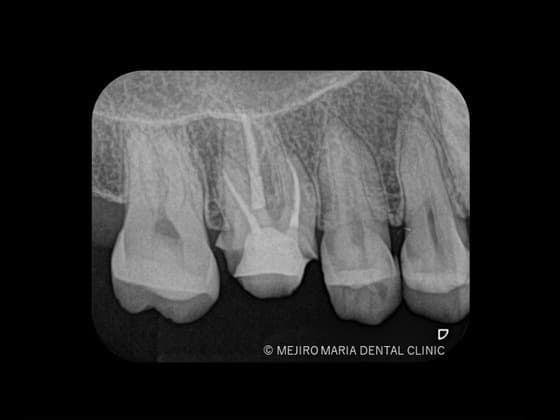

レントゲンの画像

歯髄が不可逆性歯髄炎なのか、可逆性歯髄炎なのかを確実に診断するためには組織切片のサンプルが必要になるため、事実上不可能です。そのため、歯髄の診断では冷たいものや温かいものなどに対する歯髄の反応を見極めることが重要になります。レントゲン、触診、温度診などの診査結果を総合的に踏まえて、現在の歯髄の状況を診断するためには、十分に診査時間を確保することが必要になります。